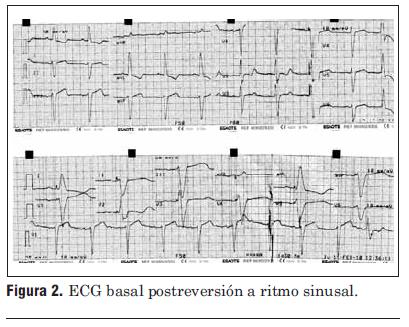

ECG postaquicardia sin elementos isquémicos agudos (figura 2). Marcadores humorales para infarto negativos. Ecocardiograma: fracción de eyección del ventrículo izquierdo 30%; sin alteraciones segmentarias de la contractilidad. Holter: extrasistolía ventricular frecuente y episodios de taquicardia ventricular no sostenida (figura 3). Cineangiocoronariografía: sin lesiones coronarias; dilatación del ventrículo izquierdo con hipoquinesia generalizada y severa disminución de la función ventricular.

Figura 2. ECG basal postreversión a ritmo sinusal.